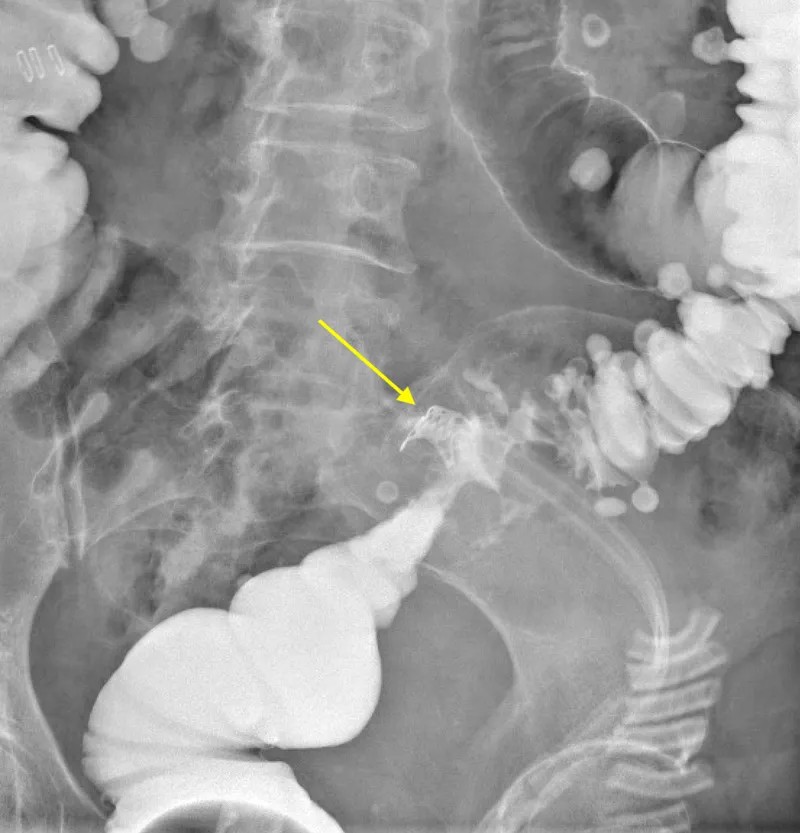

- CT Scan (Abdomen/Pelvis) with Contrast:

- IV contrast: Identifies abscesses, inflammation, and perfusion defects.

- Oral or Rectal contrast: (Water-soluble, e.g., Gastrografin) Directly visualizes contrast extravasation from the lumen.

- CT scan with oral or rectal contrast is the diagnostic gold standard, showing fluid collections or contrast extravasation.